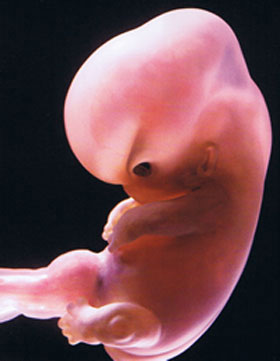

What does the future baby look like?

The largest parts of the body are the head and torso. The arms and legs are tiny processes with tubercles-fingers. The size of the fetus (more precisely, the embryo) in the 6th obstetric week reaches 4 mm, weight - up to 2 g. And here is how it develops:

• limbs gradually lengthen, knee and elbow bends are outlined;

• fingers grow a little;

• cartilaginous structures develop, that is, future bones;

• the formation of the brain begins, the bone marrow is in its infancy;

• the external genitalia are hardly outlined;

• the inner ear begins to develop;

• thymus (thymus gland) is formed, the most important organ of immunity;

• lungs, heart, liver, stomach and pancreas continue to develop;

• the neural tube becomes the embryonic nervous system;

• muscle tissue is still developing rapidly.

The tiny heart regularly counts about 140 beats per minute. Is it a lot or a little? There is such a law in nature - the smaller the heart of a living creature, the faster it beats. Therefore, such a “pulse” in the embryo is in the order of things. So far, only a specialist can determine the heartbeat during an ultrasound.

By the way, the baby has a tiny tail. This is like a reminder that we are all children of Nature (after all, many living beings have tails on Earth). A little later, the tail will be pulled in and become the tip of the spine.

And here is a new miracle - the placenta is developing, the umbilical cord is forming. The baby is no longer pressed close to the wall of the fetal egg. He swims freely in the amniotic fluid and makes his first movements. But mother will not be able to feel it very soon. But she feels a lot more.